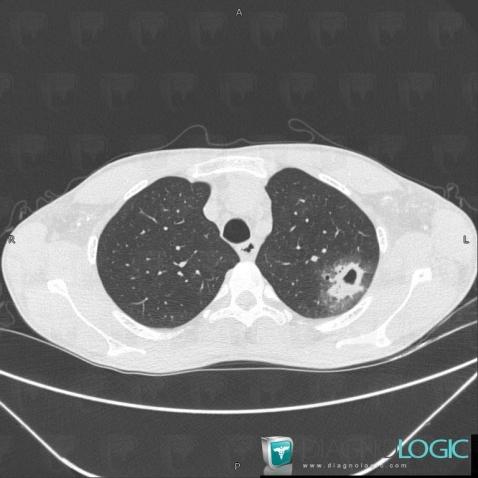

Aspergillosis, Pulmonary parenchyma, CT

Here is the specific information in the key image above:

- Diagnosis Aspergillosis, Location(s) Pulmonary parenchyma, with gamuts Pulmonary nodule with halo of ground glass opacity, Cavitary pulmonary nodule, Peripheral and sub pleural zone disease, Sub pleural pulmonary nodule